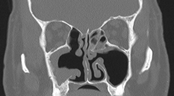

The patient was kept under regular follow up when in the year 2012 he was noticed to have soft granulation tissue arising from right middle meatus and extending to the nasal cavity. The CT scan confirmed a soft tissue opacification of right maxillary sinus extending to the right nasal cavity (Figure 4). He underwent FESS and intra-operatively a large polypoid mass extending from right maxillary sinus to nasal cavity was removed. No macroscopic residual mass was observed with 45 and 70degree endoscopic examination. Histological examination of the right middle meatus polypoidal mass confirmed the presence of Schneiderian papilloma of exophytic subtype. He has been followed up regularly since then. He is asymptomatic and to date have been recurrence free at 2years of follow up, both clinically and radiologically (Figure 5).

Figure 4 Right maxillary sinus IP recurrence (Year 2012).